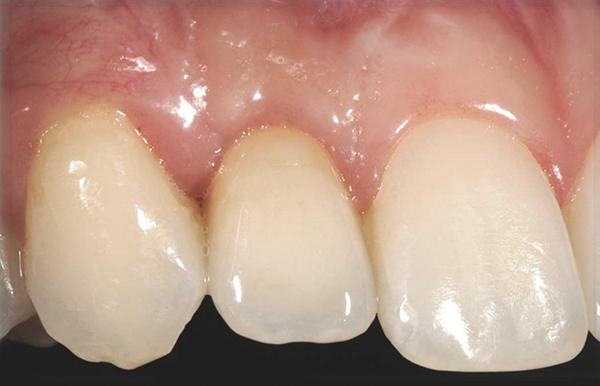

Fig 25. The final crown in place 6 months after implant insertion.

Figure 25